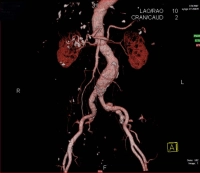

En el ejemplo de película se trata de un AAA infrarrenal cerrado con un diámetro de > 5 cm: